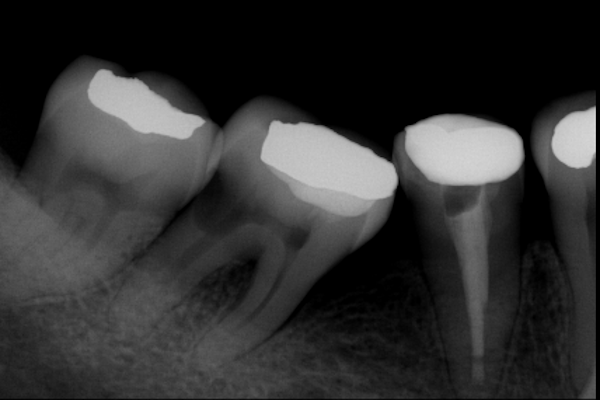

Paciente con infección de pulpa dental con dolor severo

Paciente masculino de 43 años de edad, con dolor severo y riesgo de pérdida de la pieza.

El paciente en su consulta de diagnóstico

El paciente feliz, al finalizar su tratamiento